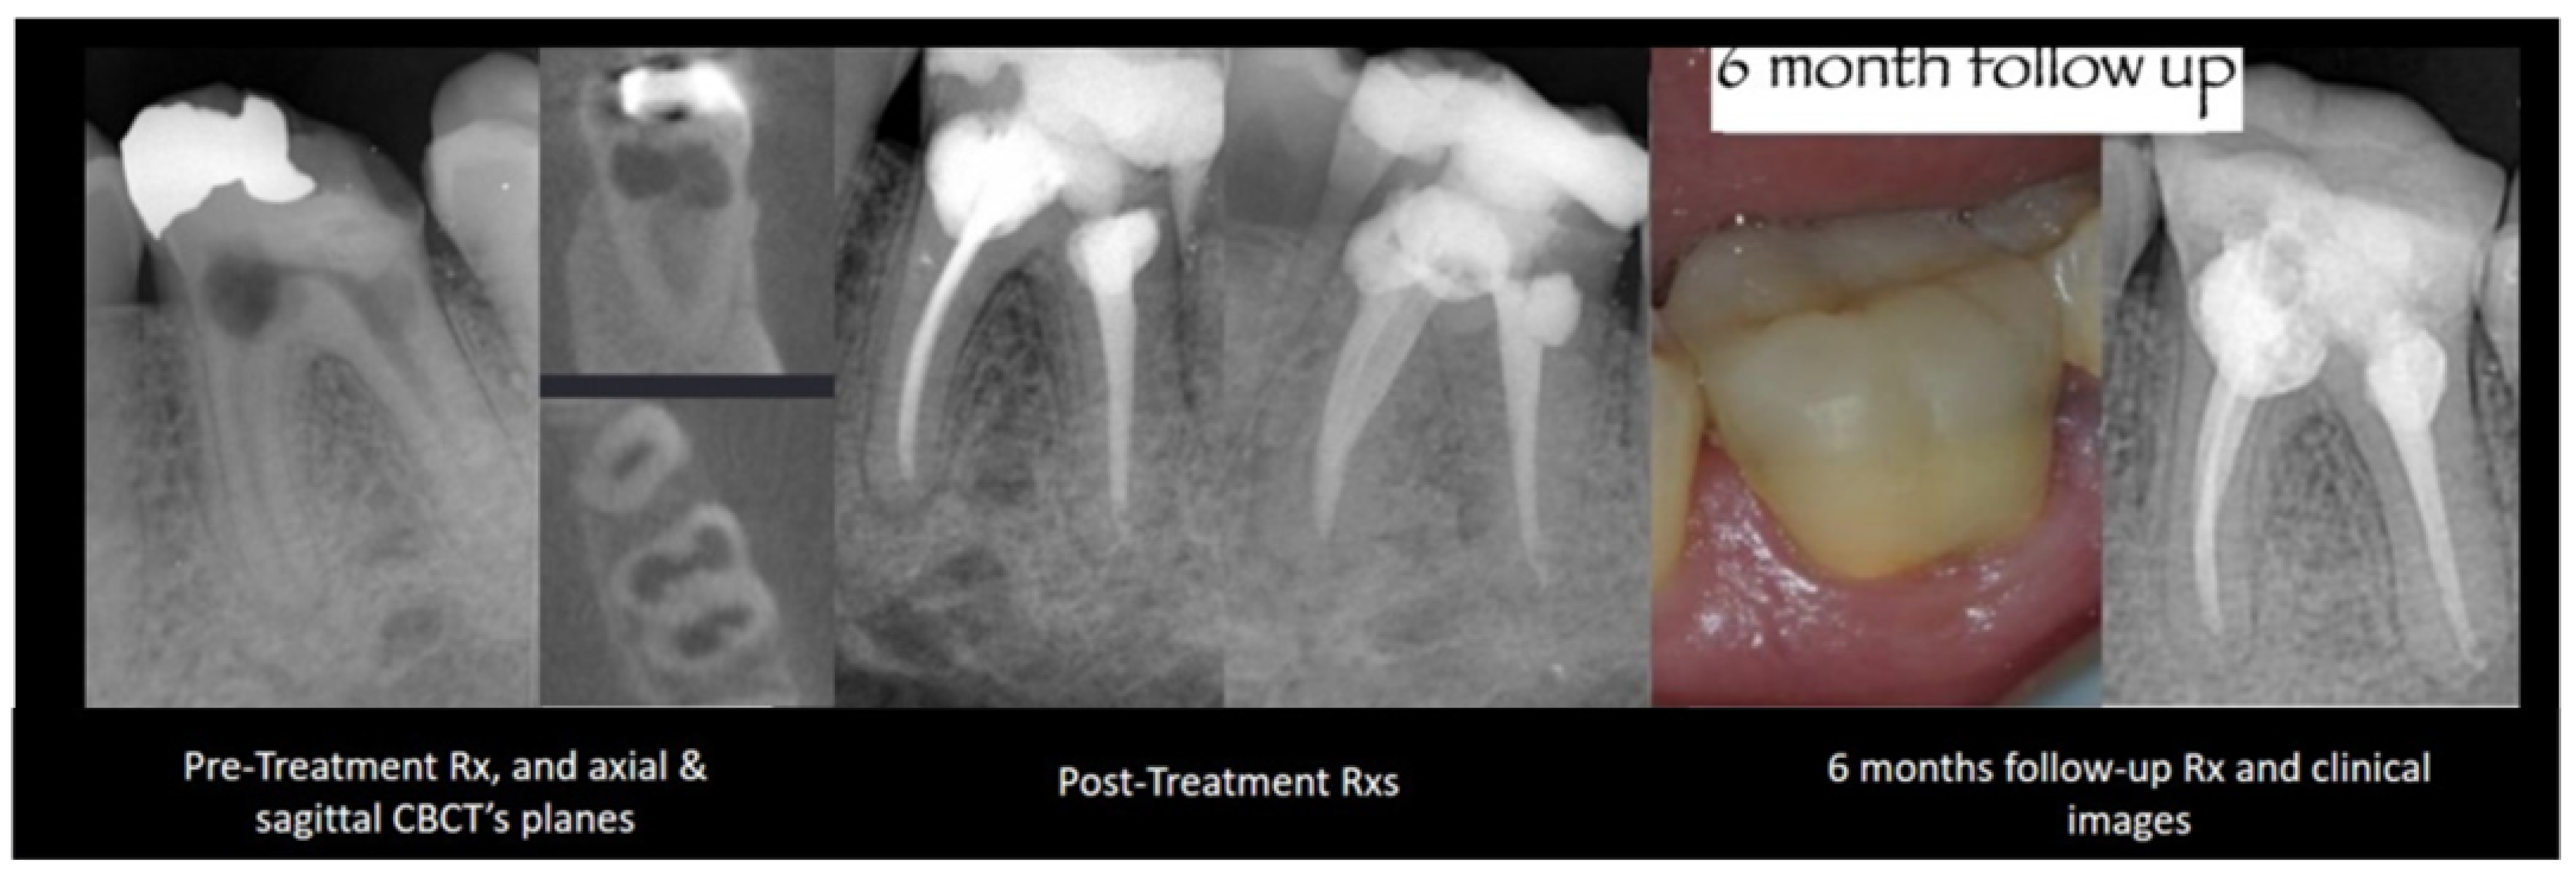

2.2. Cracked Tooth

2.4. Resorptions